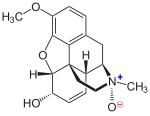

Nitrogen morphine derivatives

- 1-Nitrocodeine cas?

- Codeine-N-oxide

- Morphine-N-oxide

Structures

| Morphides | ||||

|---|---|---|---|---|

1-Nitrocodeine 1-Nitrocodeine |

Codeine-N-oxide Codeine-N-oxide |

Morphine-N-oxide Morphine-N-oxide | ||